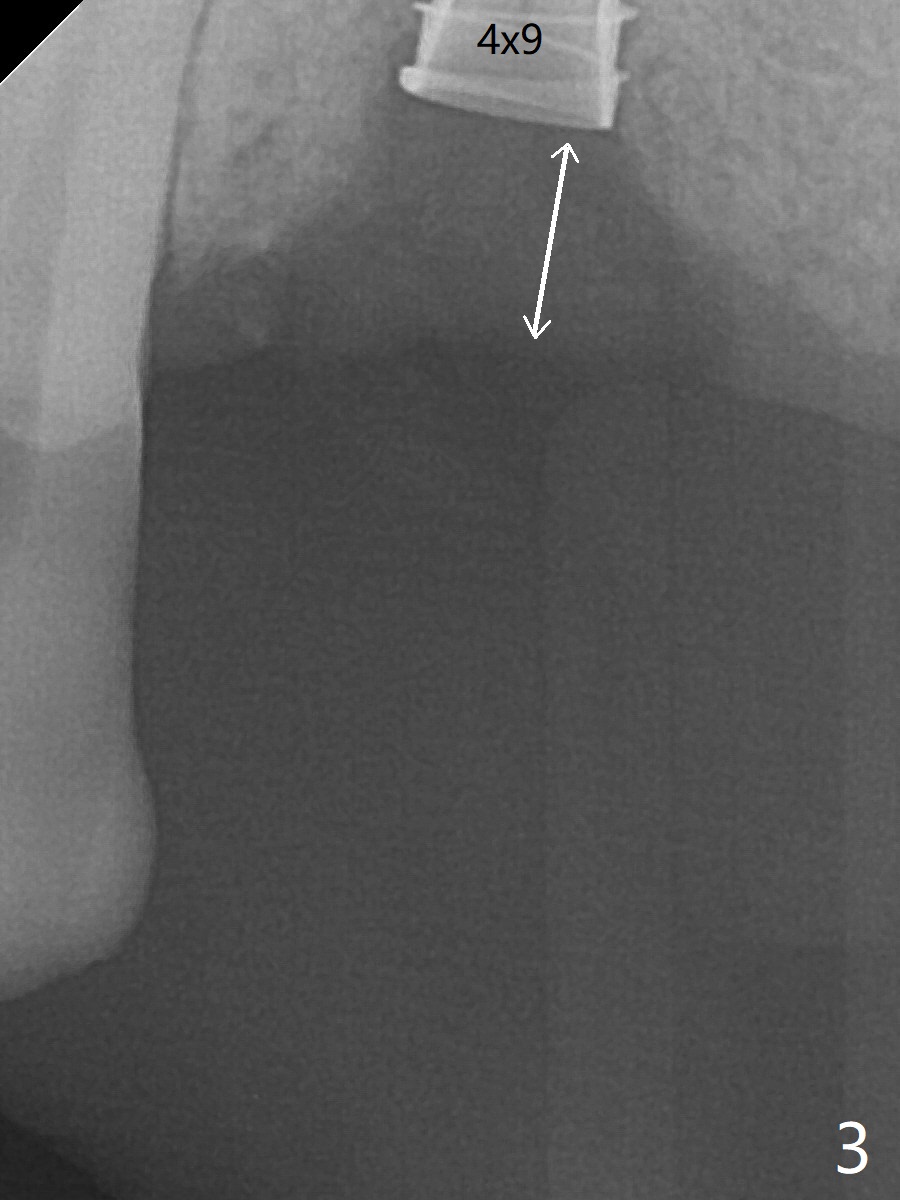

Five months post implant removal and bone graft, incision is made at #12. Osteotomy is being done with guide until 3.0x7.3 mm drill with 1 O-ring (palatal wall being thin), followed by 3.2x17-19 mm sinus round drills and 2.2x11.5 mm drill. After placement of 2 small loads of bone graft, a 4x9 mm dummy implant is inserted for sinus lift (Fig.1,2 *). By this time, the buccal plate is gone, while there is apparently the palatal periosteum. With more bone graft for sinus lift, a 4x9 mm final implant is placed with 30 Ncm (machine) and 4 mm subgingival (Fig.3,4 double arrows). Sticky bone (Fig.5,6 *) is applied around the coronal end of the implant and cover screw (S), followed by 2 pieces of PRF and 4-0 PGA suture. The sutures appear to have been dissolved and PRF membrane exposed 7 days postop (Fig.7,8 (smoker)). Four months postop, the wound heals except a small hole, which seems to be communicated with the underlying implant (Fig.9). The sinus lift remains (Fig.10 <), while bone loss appears to be present around the implant (Fig10,11 *). After placement of 5.5x4 mm healing abutment and before suturing, allograft is pushed into periimplant space (Fig.12, 13 *).